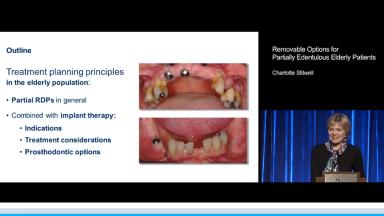

Charlotte Stilwell explains treatment-planning principles in the elderly population regarding partial removable dental prostheses (RDPs) in general as well as the combination of partial RDPs with implants. General partial RDP concepts include indications, prosthodontic advantages, and hygienic design and maintenance. Evidence is presented on the advantages and longevity of the shortened dental arch.

This lecture also gives an overview of implant-assisted partial RDPs, addressing support, retention, and esthetics in combination with tooth replacement, ridge preservation, and full-arch conversion. Unsplinted and splinted implant prosthodontic options for retention are presented. Finally, emphasis is placed on the importance of using implants as part of longer-term planning for the patient’s dentition.

At the end of this Congress Lecture you should be able to…

- discuss treatment planning for partial RDPs

- describe factors affecting implant-assisted partial RDPs

- outline prosthodontic options for implant-assisted partial RDP retention